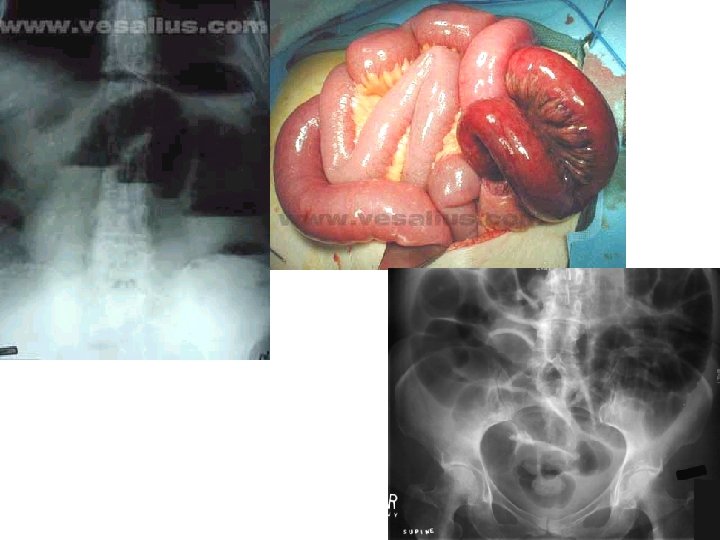

OCCLUSIONE INTESTINALE ARRESTO PATOLOGICO DELLA PROGRESSIONE DEL CONTENUTO GASTRO ENTERICO. EZIOPATOGENESI A) ILEO MECCANICO: presenza di un ostacolo anatomico. B) ILEO ADINAMICO/PARALITICO: paralisi della muscolatura intestinale con perdita del tono e della peristalsi.

ASPETTO ANATOMO-FISIOLOGICO A) ileo meccanico: - a monte del’ostacolo dilatazione delle anse con ristagno di materiale. A valle l’intestino mantiene le sue caratteristiche morfo funzionali normali. La peristalsi è mantenuta. -nell’ileo complicato da strangolamento, le caratteristiche del tratto intestinale occluso sono quelle dell’infarto intestinale. B) ileo adinamico: -diffusa distensione dell’intestino -assenza di peristalsi Ileo meccanico nel tempo può evolvere in quello paralitico assumendone tutte le caratteristiche

FLUSSO DIAGNOSTICO STRUMENTALE • Paziente “urgente”: Rx addome in bianco ecografia addominale • Paziente in elezione clisma opaco Rx vie digerenti con mezzo di contrasto

QUADRO RADIOLOGICO: Rx addome in bianco • Ileo meccanico: -distensione meteorica delle anse a monte dell’ostruzione -livelli idroaerei -mantenimento delle pliche circolari • Ileo paralitico: -distensione meteorica diffusa o di alcuni settori addominali -contorno liscio delle anse -livelli idroaerei tardivi